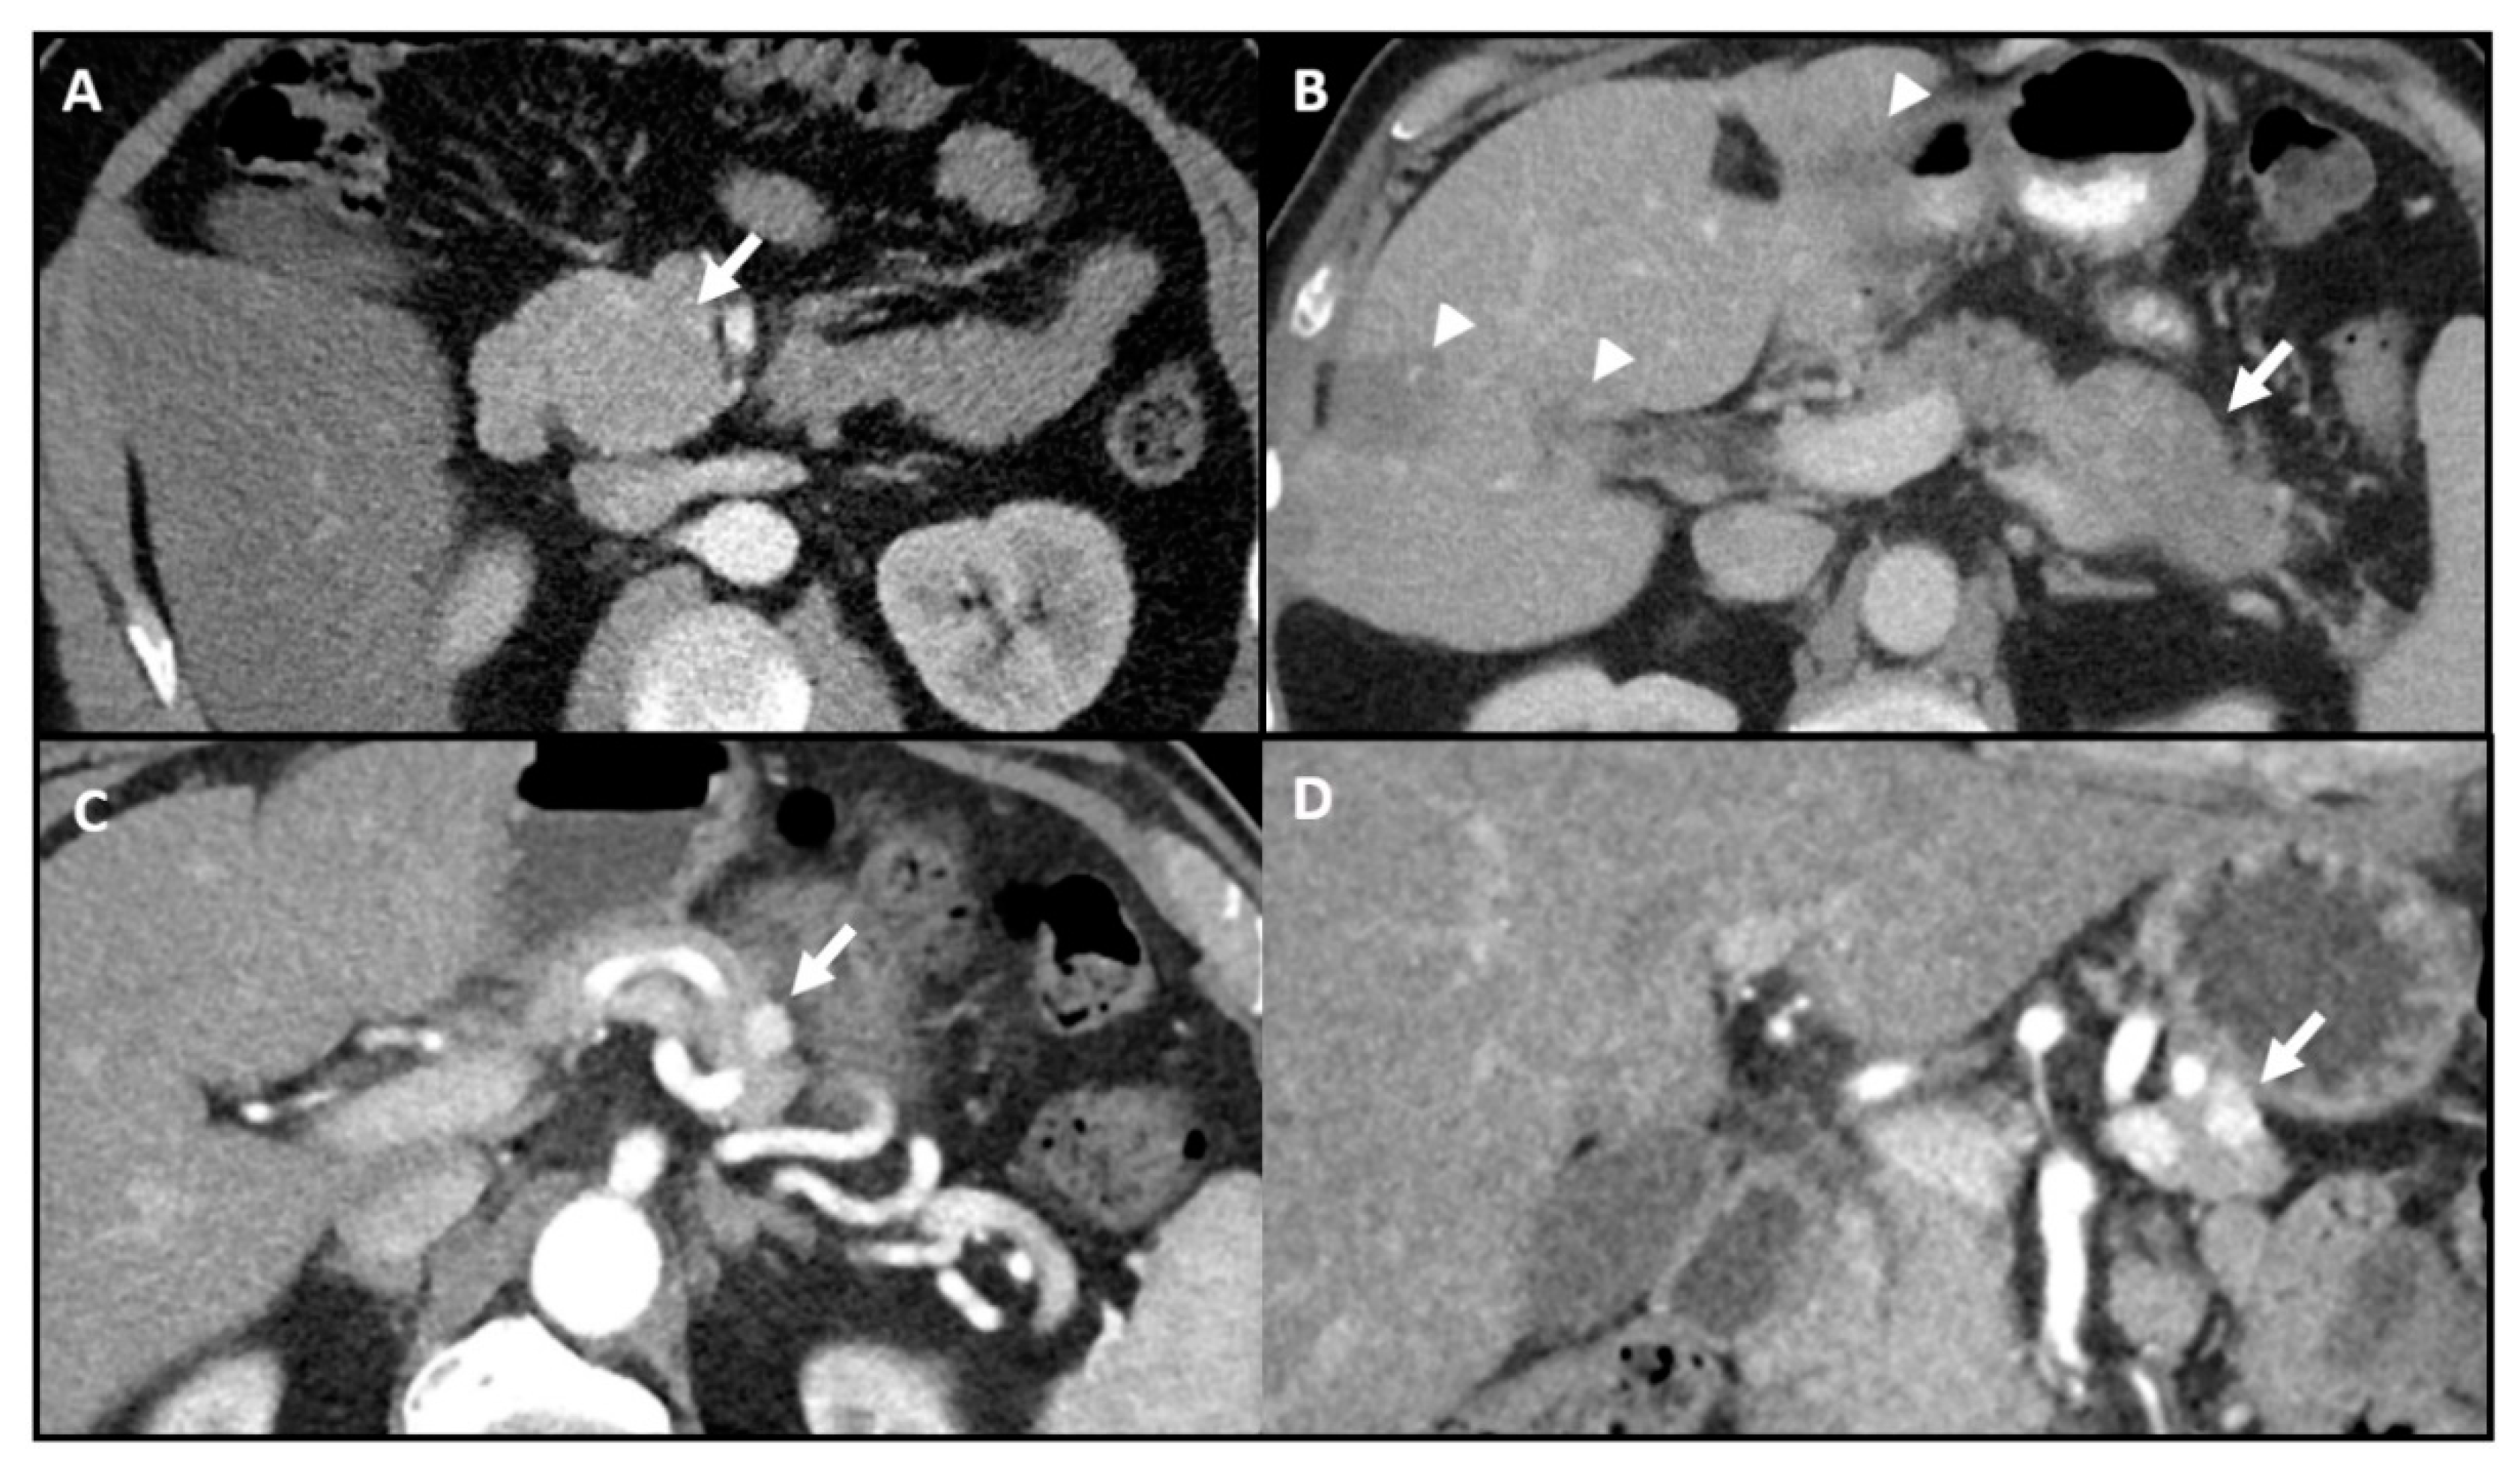

- Fidler, J.L.; Fletcher, J.G.; Reading, C.C.; Andrews, J.C.; Thompson, G.B.; Grant, C.S.; Service, F.J. Preoperative Detection of Pancreatic Insulinomas on Multiphasic Helical CT. Am. J. Roentgenol. 2003, 181, 775–780. [Google Scholar] [CrossRef] [PubMed]

- Gouya, H.; Vignaux, O.; Augui, J.; Dousset, B.; Palazzo, L.; Louvel, A.; Chaussade, S.; Legmann, P. CT, endoscopic sonography, and a combined protocol for preoperative evaluation of pancreatic insulinomas. Am. J. Roentgenol. 2003, 181, 987–992. [Google Scholar] [CrossRef] [PubMed]

- Thompson, S.M.; Vella, A.; Service, F.J.; Grant, C.S.; Thompson, G.B.; Andrews, J.C. Impact of variant pancreatic arterial anatomy and overlap in regional perfusion on the interpretation of selective arterial calcium stimulation with hepatic venous sampling for preoperative localization of occult insulinoma. Surgery 2015, 158, 162–172. [Google Scholar] [CrossRef][Green Version]